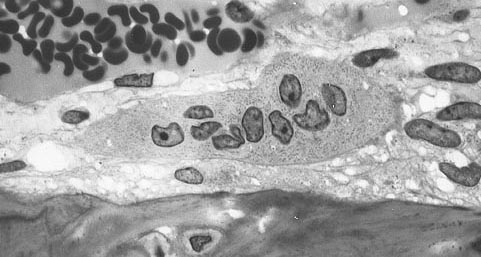

Bone marrow derived cells with bone below it showing the typical distinguishing characteristics of the osteoporosis cells: large cells with multiple nuclei and a `foamy' cytosol.

Pictures illustrating the onset of osteoporosis.